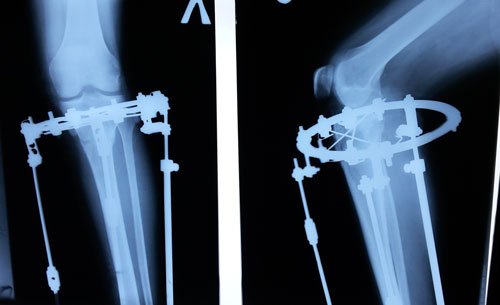

Re: Терачина♥♥♥

Дата операции 03.12.2015г.

Дата снятия аппаратов 09.03.2016г.

Срок лечения 95 дней.